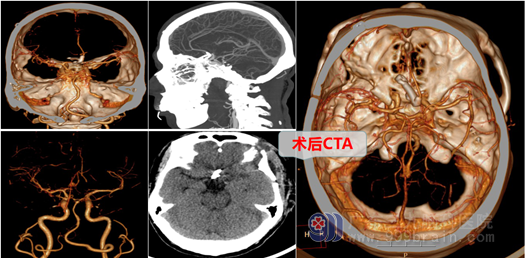

由于当地医院不具备进行脑动脉瘤手术的条件,医生建议他立即转广州大医院进行治疗。他儿子救父心切,一刻也不敢耽搁,在多方打听之下,慕名来到广东三九脑科医院外十科。接诊的樊医生在详细问诊后,立即收入院并安排进行相关的检查。检查结果出来之后,樊医生跟高大叔的儿子详细的讲解了他的病情。高大叔脑袋里确实长了一个动脉瘤,大约21.6*18.3cm,大概有鹌鹑蛋这么大呢。动脉瘤一旦确诊,就必须尽快手术,避免动脉瘤破裂出血造成神经功能障碍,甚至是付出生命。

动脉瘤开颅夹闭手术,也是神经外科风险巨大的挑战之一。外十科团队在科主任欧阳辉教授的带领下,对高大叔的病情进行了详细的术前讨论,并设计了慎密的手术方案。入院的第六天,儿子目送他进入手术室。 外十科团队团结协作,手术历时8小时,最终在高清显微镜下将“不定时炸弹”—颅内动脉瘤成功夹闭。